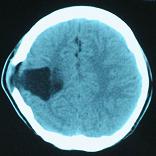

头颅CT和MRI可见颅骨缺损区下方软脑膜囊肿、脑软化灶或脑室穿通畸形(图2)。

图2:①和②CT及骨窗相显示右顶部颅骨缺损,其下方脑组织呈低密度改变;③-⑥MRI右顶局部颅骨缺如,脑组织轻度向外膨隆,右顶叶侧脑室体部旁局部脑组织缺如,代之以囊性长T1、长T2信号。

结果及随访:术后一周复查头颅CT显示脑室穿通畸形明显缩小(图6)。随访3年,未出现癫痫发作。得到很好的治疗,回归社会,正常生活学习工作。

图6:术后一周复查头颅CT显示脑室穿通畸形明显缩小